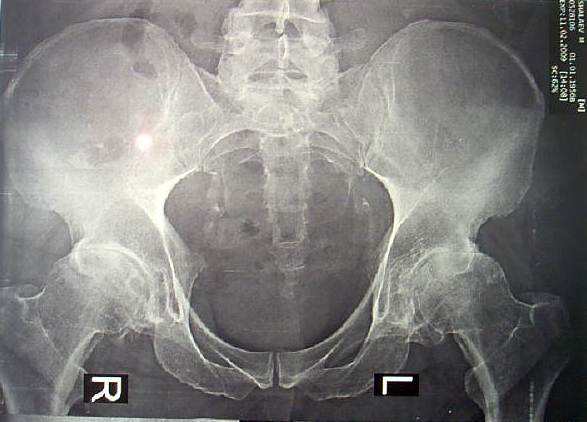

Больному 52 года, среднего роста, весит 110 кг. Около 12 лет болеет подагрой. Движения в т/б суставах ограничены и болезненны. В течении 2 лет периодически получает дипроспан  по 1.0 в каждый сустава (каждые 1.5-2 месяца). От эндопротезирования категорически отказывается, просит восстановить его сустав другими методами.

Вложение не в текстовом формате было извлечено…

Имя     : CAM_1532.JPG

Тип     : image/jpeg

Размер  : 38233 байтов

Url     : http://weborto.net:8080/pipermail/ortho/attachments/20090215/da131844/attachment-0003.jpeg